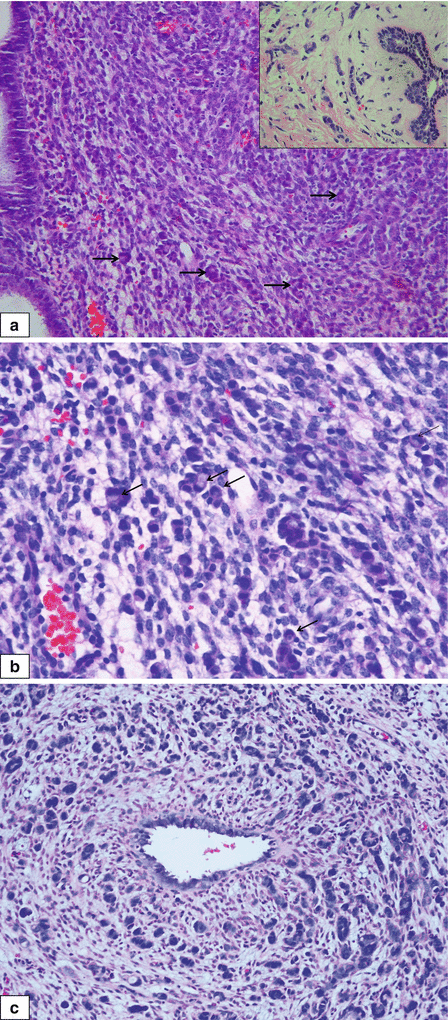

Lobular Lesions Lobular Neoplasia Invasive Lobular Carcinoma